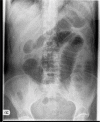

Acute appendicitis is a common surgical problem however the diagnosis is often overlooked when it presents as a small bowel obstruction. In this report we present two cases of elderly patients who presented with small bowel obstruction and raised inflammatory markers. Both patients were successfully treated with a laparotomy, adhesiolysis and appendicectomy and went on to make a good recovery.